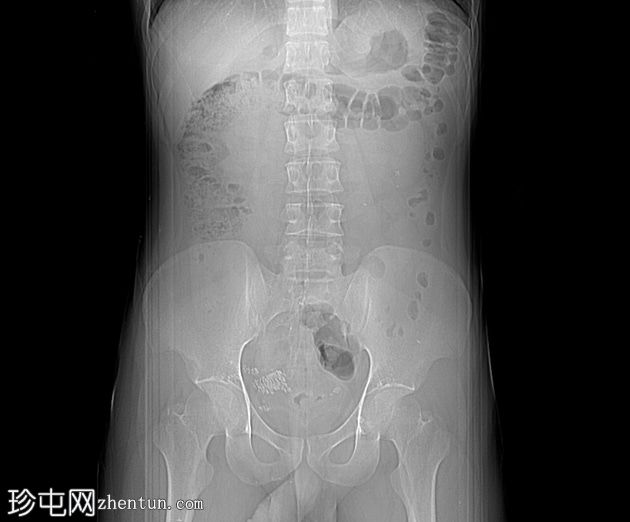

腹部平扫及输尿管膀胱平片(KUB)

右肾上盏内可见多发微小结石。

左肾上盏内可见一枚孤立性微小结石。

左侧输尿管远端,距膀胱输尿管连接处(VUJ)近端约4 cm处,可见一枚边界清晰的结石,最大轴向直径约14mm,导致轻度左侧输尿管肾积水。

未见明显的肾周脂肪浸润。

未发现其他急性腹腔或盆腔异常。

本病例显示双侧肾脏微结石,以及左侧输尿管远端距膀胱输尿管连接处约 4 cm 处的高密度结石(平均密度约为 1206 HU),符合钙结石的特征。

轻度上游输尿管肾积水提示存在部分梗阻。结石大小是预测其能否自行排出的关键因素,小于 5 mm 的结石通常无需干预即可自行排出。